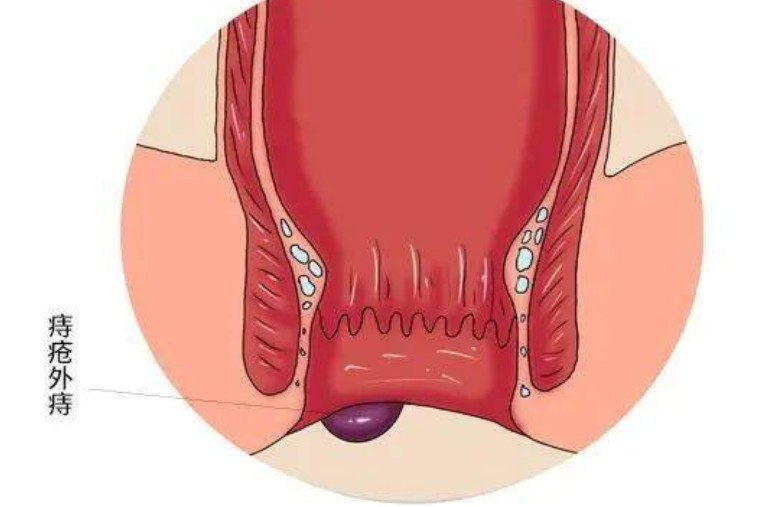

外痔圖片

A:痔瘡分為內痔、外痔、混合痔,外痔就是生長在齒狀線以下的一種腫物。這種疾病一般是由炎症以及靜脈迴流等原因所導致的,當病人患上外痔以後一般是可以看得見的,並且這種痔瘡不容易出血。如果病人讓腫塊受到摩擦的話,可能會病人出現疼痛等症狀。臨床上如果……

A:痔瘡是常見的肛周疾病,它是由直腸下段或肛管周圍的黏膜曲張靜脈造成。根據解剖位置的不同,齒狀線以上稱之為內痔,齒狀線以下稱之為外痔。外痔在臨床上大致可分為血栓性外痔、血管源性外痔、炎性外痔,以及結締組織性外痔。血栓性外痔大多是在外痔的血管團……

A:外痔的發生原因是由於長時間的便秘或者反覆的腹壓增高,影響到了肛周靜脈血液迴流,而隨著病情的演變會導致局部形成曲張的靜脈團,而在勞累之後或者暴飲暴食之後,會誘發急性血栓形成,所以就會表現為肛周的暗紫色的腫物,急性血栓性外痔經過有效的治療萎縮之……